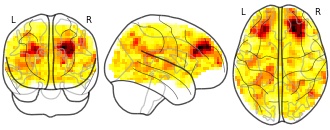

EmailClick to copy linkLink copied Cite(2021). Developmental differences in the brain response to unhealthy food cues: an fMRI study of children and adults: Correlation with SDS BMI and healthy vs unhealthy food viewing in children [Dataset]. http://identifiers.org/neurovault.image:68426niftiAvailable download formatsUnique identifierhttps://identifiers.org/neurovault.image:68426Dataset updatedMar 1, 2021License

License information was derived automaticallyDescriptionCorrelation between standardized BMI (in kg/m2) and activation in response to healthy compared with unhealthy food viewing in children (n = 27). Corrected for age and gender.

Food cues are omnipresent and may trigger overconsumption. In the past 2 decades, the prevalence of childhood obesity has increased dramatically. Because children's brains are still developing, especially in areas important for inhibition, children may be more susceptible than adults to tempting food cues.We examined potential developmental differences in children's and adults' responses to food cues to determine how these responses relate to weight status.We included 27 children aged 10-12 y and 32 adults aged 32-52 y. Functional magnetic resonance imaging data were acquired during a food-viewing task in which unhealthy and healthy food pictures were presented.Children had a stronger activation in the left precentral gyrus than did adults in response to unhealthy compared with healthy foods. In children, unhealthy foods elicited stronger activation in the right inferior temporal and middle occipital gyri, left precentral gyrus, bilateral opercular part of the inferior frontal gyrus, left hippocampus, and left middle frontal gyrus. Adults had stronger activation in the bilateral middle occipital gyrus and the right calcarine sulcus for unhealthy compared with healthy foods. Children with a higher body mass index (BMI) had lower activation in the bilateral dorsolateral prefrontal cortex while viewing unhealthy compared with healthy foods. In adults there was no correlation between BMI and neural response to unhealthy compared with healthy foods.Unhealthy foods might elicit more attention both in children and in adults. Children had stronger activation while viewing unhealthy compared with healthy foods in areas involved in reward, motivation, and memory. Furthermore, children activated a motivation and reward area located in the motor cortex more strongly than did adults in response to unhealthy foods. Finally, children with a higher BMI had less activation in inhibitory areas in response to unhealthy foods, which may mean they are more susceptible to tempting food cues. This trial was registered at www.trialregister.nl as NTR4255.